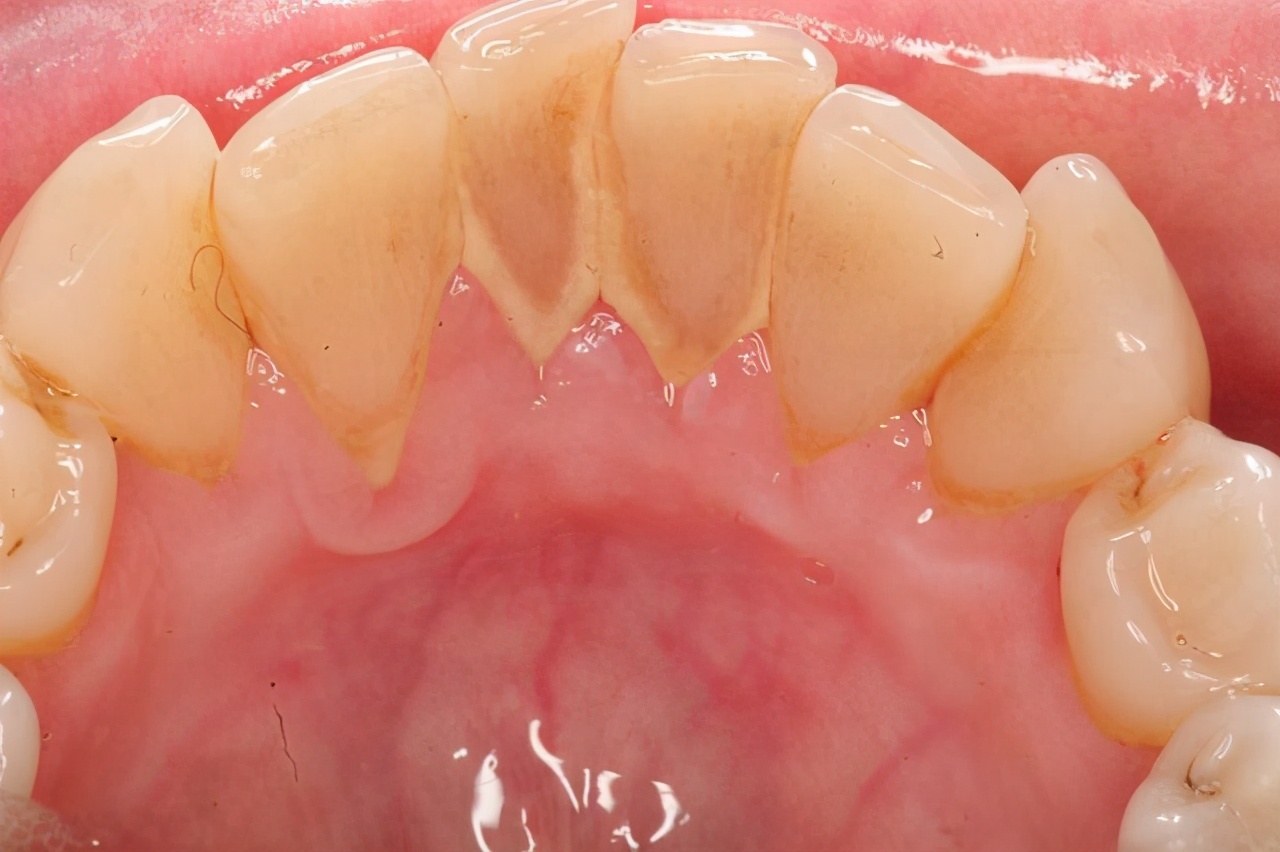

有的人说:为什么能从嘴里抠出黄泥,或者是硬硬的物质。这些都是牙结石,它是由口腔中的钙以及细菌沉积造成的结果,并不会因为每天几次刷牙就能够解决。

口腔内无时无刻都会积攒大量的细菌,而它们随着时间的推移,好比“滴水穿石”一般,时间越久积累的程度也就越严重。此外,还会因为每次刷牙刷不到的地方,牙结石也会粘附在牙齿上,最终成为刷不掉的结石。

至于洗牙所产生的不适,确实是一个小问题,尤其是已经长牙结石的人群,它们喜欢寄居在牙齿和牙龈的交界部位,洗牙的过程中接触过多,肯定会产生不适。不过,大家只要忍住过会儿便能好转。